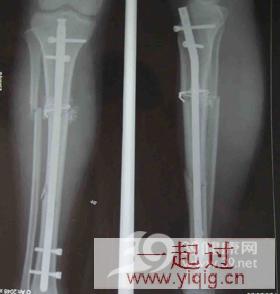

一年前,我因车祸出现小腿骨折,诊断为右胫骨中下段粉碎性骨折。当时医生给我做了手术,打了钢板,出院前拍了X光片,医生说骨折对位线良好。出院后,我一直拄拐杖走路。最近,我到医院复查,拍X光片提示骨折未愈合。我不明白,为何骨折一年了都愈合不了?

从你描述的症状来看,可初步诊断为“胫骨骨折术后骨不连”。出现这种情况,可能与下面几个因素有关:

首先,你的骨折之所以久久不愈合,可能跟骨折部位有关。胫骨骨折后骨不连的发生率本来就比较高,且大多发生于胫骨中下段。究其原因,主要是胫骨中下段血管分布相对稀少,骨折后对局部血运已经造成了破坏,而手术中广泛剥离骨膜,会使骨折部的血供破坏严重,从而造成骨不连。

此外,胫骨粉碎性骨折在复位与固定过程中,会发生一些小碎骨块的丢失。如果在清理创口的过程中造成过多的碎骨块丢失,会导致产生较大骨缺损,最终也会发生骨不连。